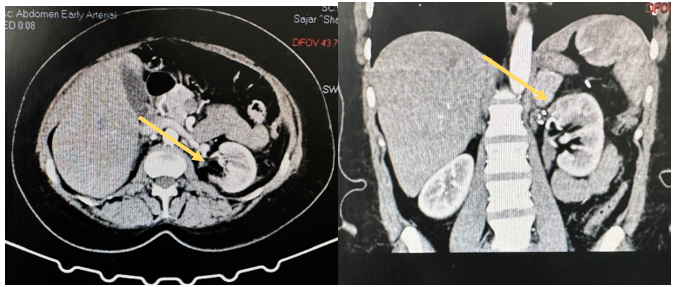

Case Two: A 46-year-old female with a history of sleeve gastrectomy, chronic anemia, and hypertension was referred to us for evaluation of left-sided flank pain. Her last imaging study, conducted 9 years ago, showed a 3 cm left renal AML. A CT scan of the abdomen and pelvis revealed a 10x9x8.3 cm lesion in the left upper pole, suggestive of AML (Figure 5). A coinciding right non-obstructing 9 mm renal stone was noted in her malrotated right kidney. The patient was counseled on her diagnosis and advised to undergo active management. Due to the limited availability of interventional radiologists and the absence of robotic services, the patient was offered an open nephron-sparing vs radical nephrectomy and she agreed on proceeding with surgical intervention. Given the floating stone in her right kidney and the planned complex partial heminephrectomy on her left kidney, we inserted bilateral double J stents at the beginning of her surgery. A left sided modified Makuuchi incision was performed, the abdomen was entered and the left colon was mobilized along with a medial visceral roll reflecting the spleen, pancreas, and stomach away from the left retroperitoneum. The omni retraction system was then deployed and the kidney was carefully dissected circumferentially. The renal hilum was dissected with subsequent exposure of the renal artery and vein. Intraoperative ultrasound was used to identify the margins around the lesion in the upper pole prior to dissection. Warm and cold ischemia was performed (total time 28 min), and the upper pole lesion was resected. Bleeding was encountered during the resection with an estimated blood loss of 300 ml. Tumor resection was then completed (Figure 6), and the encountered vessels were ligated individually with 5-0 Prolene. Calyceal defects were closed individually with 5-0 PDS, the renorrhaphy was completed in two layers with bolstering sutures in a horizontal mattress manner using 2-0 PDS with Surgicel®. After renorrhaphy and securing hemostasis, nephropexy to the lateral wall and an omental wrap over the resected kidney was performed, and a 19F JP drain was placed. The patient was discharged on post-operative day 7, with her drain removed after demonstrating a normal creatinine level. She was followed up at the OPD, and the pathology report showed classic AML. Her double J stent was removed 6 weeks after surgery with right sided ureteroscopy and stone lithotripsy. The procedure was uneventful and both stents were removed successfully.

Figure 5. CT Imaging demonstrating a large Lt Kidney AML.